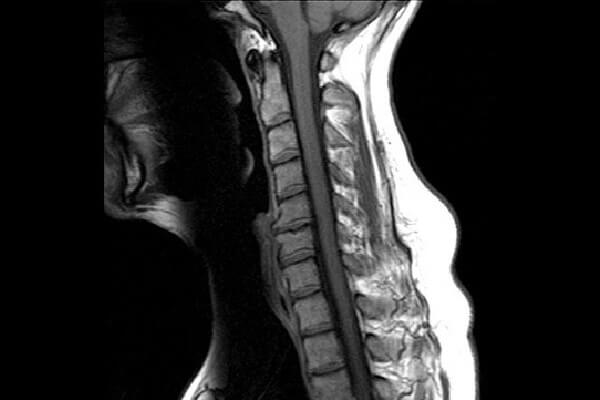

علاوه بر اشعه ایکس پزشک می تواند از MRI برای تشخیص بیماری استفاده کند.

این آزمایش تصویربرداری از امواج رادیویی و یک میدان مغناطیسی برای ایجاد تصاویری از استخوان و بافت نرم استفاده می کند.